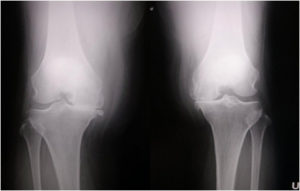

変形性膝関節症(両側同時人工膝関節置換術)

手術前